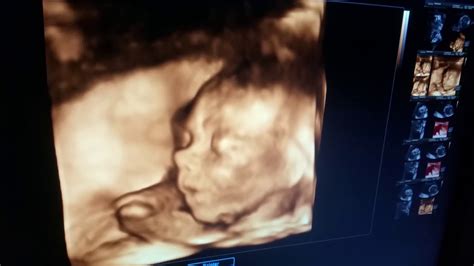

În săptămâna 20 de sarcină se recomandă efectuarea morfologiei de trimestrul 2. Este vorba despre o ecografie detaliată care permite efectuarea de măsurători pentru a monitoriza evoluția și dezvoltarea bebelușului, identificarea și evaluarea principalelor organe și sisteme de organe din corpul fătului și modul în care funcționează acestea.

Tot în cadrul morfologiei de trimestrul 2, medicul obține informații importante despre cantitatea de lichid amniotic și despre modul de funcționare a placentei.

Se poate stabili, la cererea părinților, care este sexul bebelușului, dacă poziția acestuia permite vizualizarea organelor genitale.